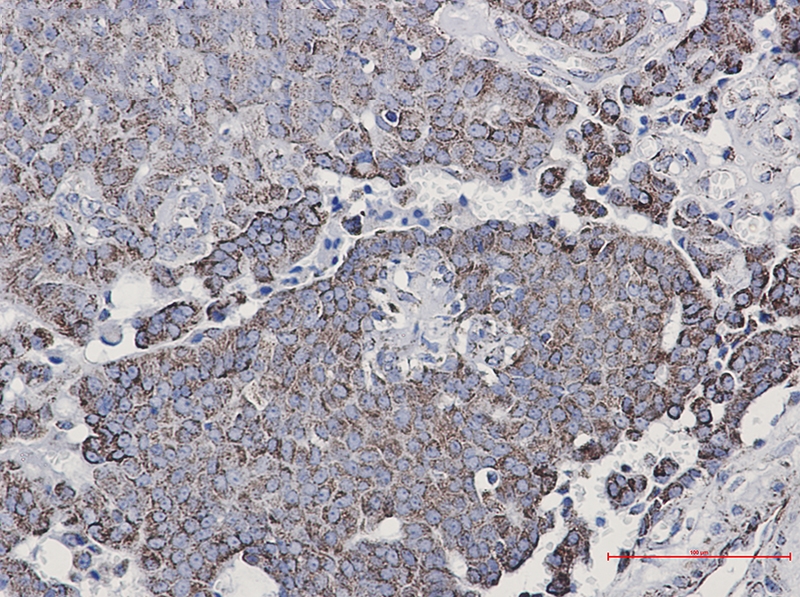

Immunohistochemistry of NDUFC2 in paraffin-embedded Human breast cancer tissue using NDUFC2 Rabbit mAb at dilution 1/50